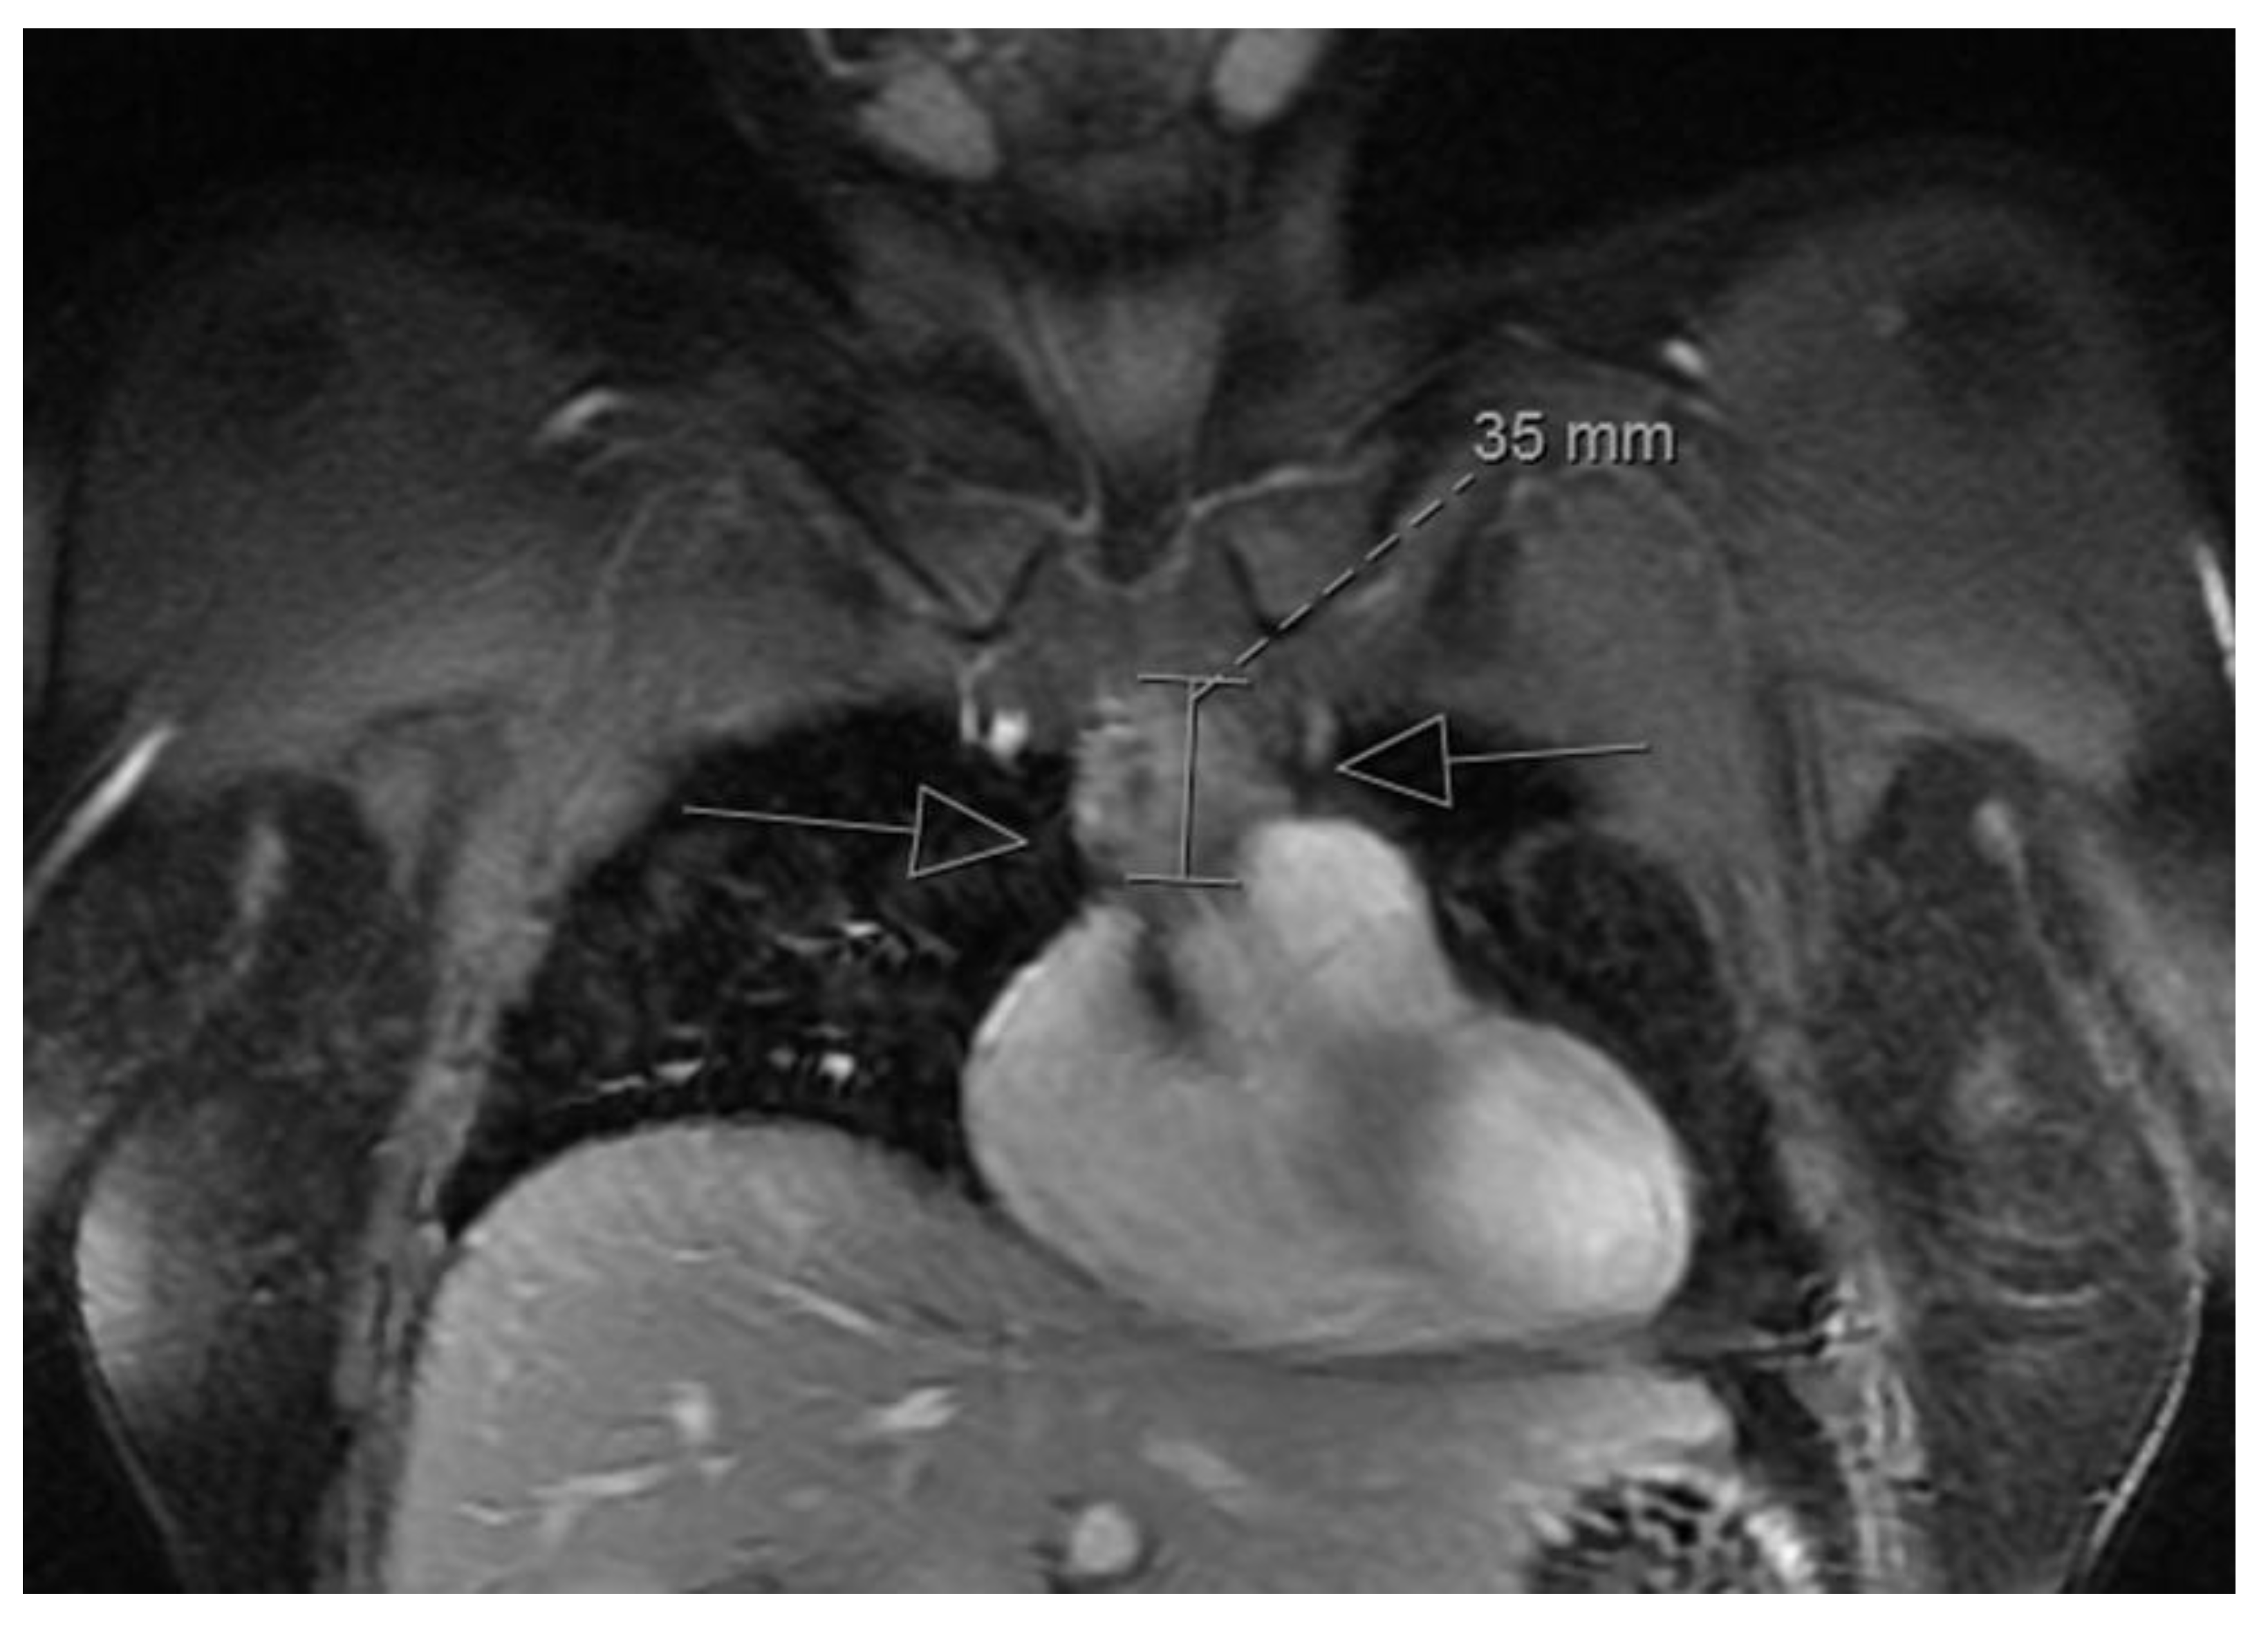

3.1. Clinical Presentation